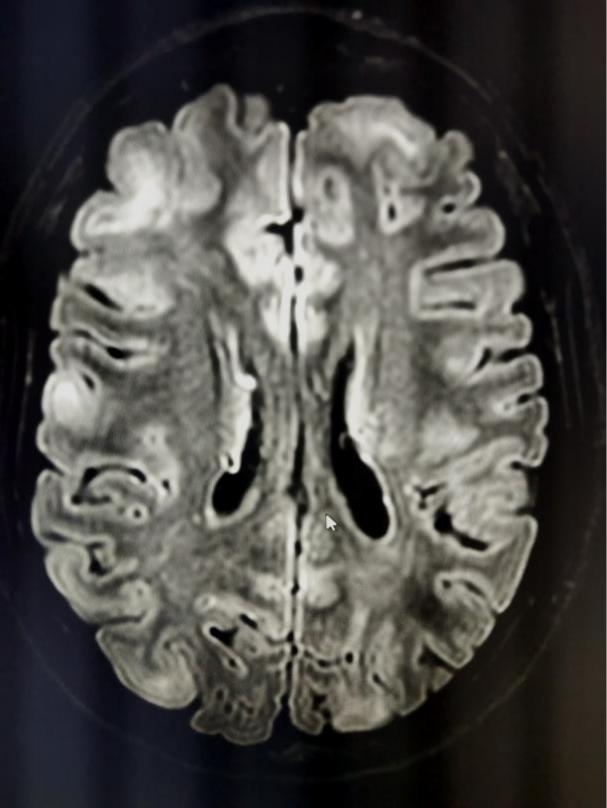

杨莹医生仔细对小王查体,发现小王鼻翼双侧及面部可见大量颗粒状皮脂腺瘤,呈淡黑色色素沉着(见图1),并不是小王妈妈口中的痘痘,同时发现小王记忆减退,智力欠佳。

图1